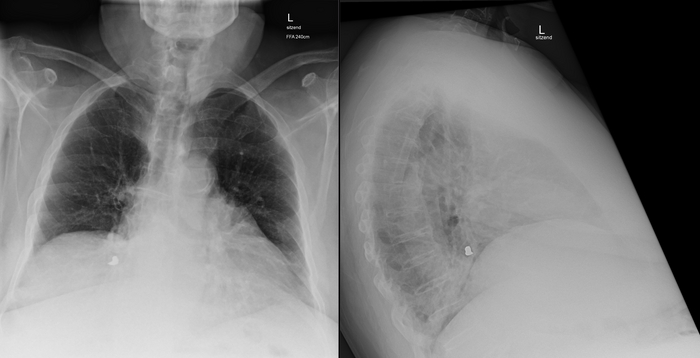

Также образование хорошо визуализируется на рентгеновских снимках, сделанных пару дней спустя:

Т.е. скорее всего имеет место быть аспирация (случайное "вдыхание") инородного тела (я предположил зубную коронку) с перекрытием бронха и развитием гиповентиляционного синдрома с пневмонией.